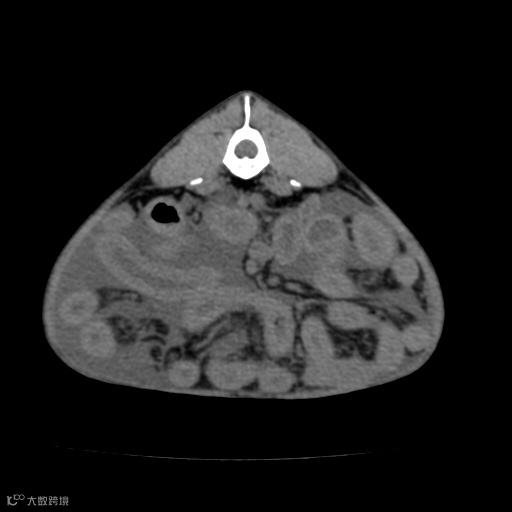

由于扫描参数、金属物体或运动等因素引起的图像畸变。评估伪影时, 应注意图像中是否存在条纹状、环状或阴影状的异常结构,以及其对图像质量和解剖结构的影响。

金属伪影

呼吸运动伪影